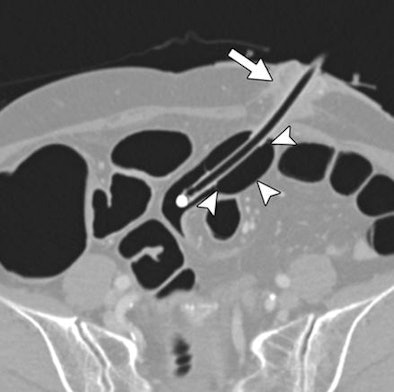

| Woman, 72, who had a sigmoid colostomy undergoes CTC. Oblique transverse CTC image shows position of catheter. Distended balloon (arrowheads) is located several centimeters beneath colostomy stoma. Short colonic segment and adjacent tissue between balloon and stoma (arrow) are squeezed as distended balloon is slightly pushed back during colonic insufflation, acting as mechanism to prevent expulsion of balloon catheter. Image republished with permission of the American Roentgen Ray Society, from AJR, October 2011, Vol. 197:4, pp. W653-W657. |

An inflated balloon was placed several centimeters below the skin for insufflation of the colon using automated CO2 distention, and "the interposed tissue acted as the mechanism for preventing balloon expulsion during colonic insufflation with carbon dioxide," the authors explained. Finally, the group documented air-fluid leaks, balloon expulsion, or complications, evaluating colonic distention on a four-point scale (4 = optimal).

"We found that trapping of a short colonic segment and adjacent tissue between the balloon and the stoma, preventing expulsion of the catheter, worked effectively at the low intracolonic pressure used in our study, as evidenced by the nonoccurrence of catheter displacement or major leakage of air or fluid during the examinations," they wrote. "It is uncertain, however, whether the same method would work successfully at a higher colonic insufflation pressure."